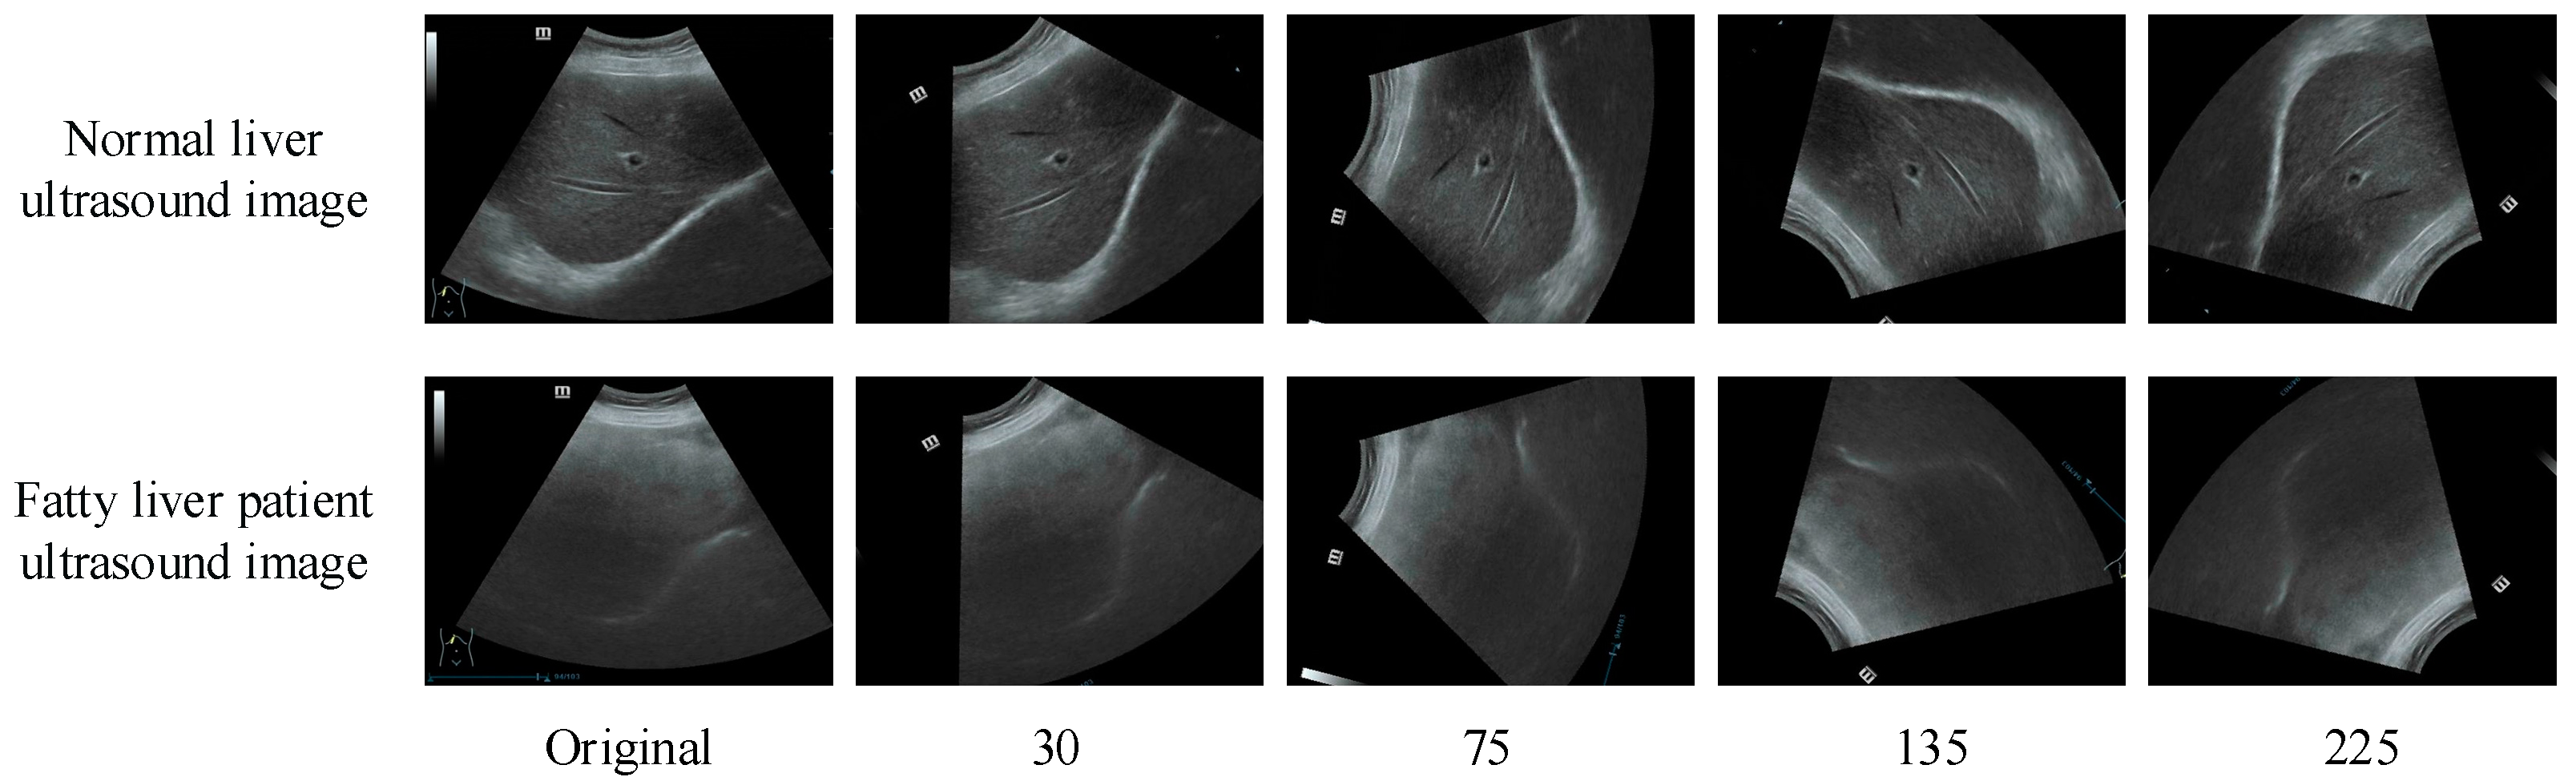

- A new dataset for fatty liver ultrasound image classification is constructed to train, validate, and test the proposed method. A total of 250 liver ultrasound images are collected in the new dataset, including 100 normal liver ultrasound images and 150 abnormal liver ultrasound images.